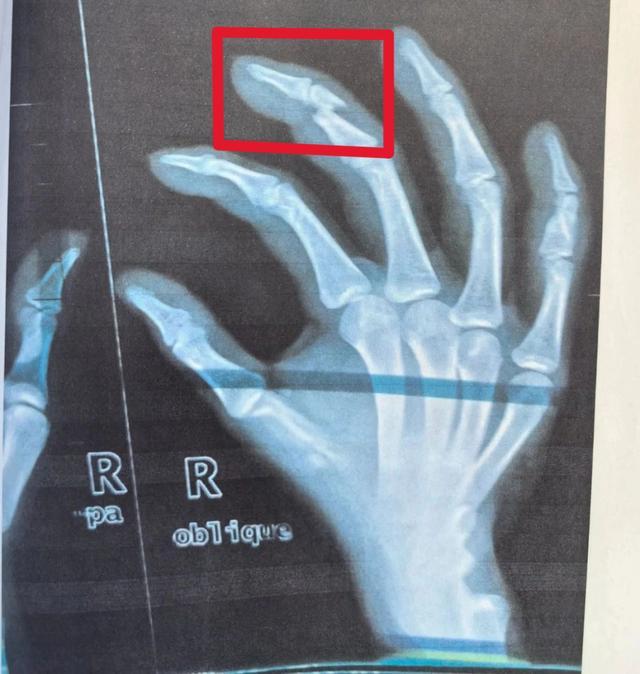

2024年3月,肖某驾驶三轮车在包头市某乐园北门不慎与一辆共享电动车相撞,电动车上的大龙、阿云二人随即倒地,阿云称自己右手指受伤,肖某便陪同二人前往医院检查,x光片显示阿云右手中指折断。

经法院调查,2023年4月至2024年3月间,阿祥、大龙、阿云三人组成诈骗团伙,专门瞄准无保险的三轮车作案。他们的“碰瓷”套路很简单,由阿祥或大龙驾车故意逼停被害人三轮车,提前自断手指的阿云则配合制造碰撞假象,并以受伤为由要求赔偿。